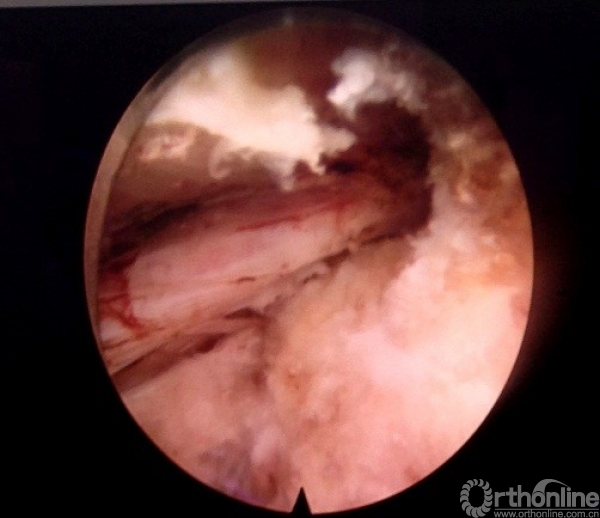

北京海淀医院微创脊柱外科,共纳入65例应用全内窥镜治疗的伴有坐骨神经痛的腰椎间盘突出症患者,随机分成行内镜手术并在神经根局部应用类固醇激素的实验组和只进行内镜手术的对照组,试验组全部采用经椎间孔入路内镜手术,在摘除突出髓核,处理纤维环并探查松解受累神经根见周围松弛无卡压后在术区局部神经根周围注入曲安奈德20mg。